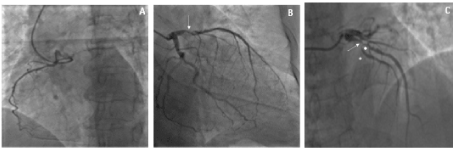

Figure 1. Basal coronary angiography of Case-1, showing hypoplastic RCA (Panel A), dominant LCX without significant stenosis (Panel B) and LAD with long sub-occlusion and bifurcating with a first diagonal branch and a septal branch compatible with “dual” LAD (Panel C).

Figure 2. Case-1: PTCA balloon dilation in LAD stenotic segment and guidewire to protect the septal large branch by the mean of a microcatheter (→) (Panel A). Retrograde spiral dissection of the LAD (*) (Dunning Classification Type II; Panel B). Stenting of septal branch and proximal LAD segment (…) (Panel B/C). Stenting of left main up to aortic root origin (Panel D). Extension spiral dissection and occlusion of LCX from the ostium (→) (Panel E). Successful and complete closure of the dissection tear associated to TIMI 3 flow (Panel F). Angio-CT scan demonstrated complete sealing of aortic dissection with complete stent patency () (Panel G) before discharge.

Figure 3. Coronary angiography at 6-mos follow-up from Case-1, demonstrating normal aortic bulb with complete stents patency and TIMI 3 flow of the LAD and LCX (Panel A/B and C).

A 77-year-old Caucasian woman affected by long-term systolic hypertension experienced typical angina and syncope during exercise and was admitted to the ED. Troponin-I was 41.9 ng/L (n.v. < 20 ng/L). Coronary angiography showed an hypoplastic right coronary artery (RCA– Figure1 - Panel A), dominant left circumflex coronary artery (LCX – Figure 1 - Panel B) without significant stenosis and left anterior descending (LAD) artery with a long sub-occlusion from the middle segment to the apex. First diagonal branch was normal and a large septal branch with angulated take-off was involved in the diseased segment (Figure 1- Panel C). Percutaneous angioplasty of LAD was performed utilizing a 3.5 Extra Backup 6F guiding catheter (Medtronic, Santa Rosa, CA, USA), and a Sion Blue 0.014” guidewire (Asahi Intecc Co., Aichi, Japan) was placed distally in the LAD. A Balance Middleweight guidewire (Abbott Diagnostics, Lake Forest, Illinois) was advanced into septal branch utilizing a Super Cross 90° microcatheter (Teleflex Medical OEM, Gurnee, Illinois) due to the acute take-off of the vessel (Figure 2 white arrow– Panel A). Then, a balloon (Euphora 2.5 x 20 mm; Medtronic, Santa Rosa, CA, USA) was inflated to nominal pressure (8 atm) to predilate LAD segment. At control angiography, iatrogenic spiral dissection of LAD was evident with retrograde extension into LM and origin of the aorta (Dunning Classification Type II [3]; Figure 2 - Panel B). Since patient’s hemodynamic was stable, a DES Ultimaster Tansei 2.75 x 13 mm (Terumo corporation, Tokyo, Japan) followed by Ultimaster Tansei 3.0 x 28 mm were deployed in an overlapping fashion (Figure 2 - Panel C) in the mid and proximal LAD segment. Then, PCI of LM was performed by implanting a first Ultimaster Tansei 3.5 x 9 mm stent at 12 atm followed by a second overlapped Ultimaster Tansei 3.5 x 12 mm stent at 18 atm up to aortic root origin, since after the first LM stent, a free intimal flap with staining contrast was still present (Figure 2 - Panel D). Then, extension of the spiral dissection to the origin of LCX, probably due to flap extension after LM stenting at high pressure inflation (Figure 2 – Panel E), was noticed. Thus, a Choice PT Extra Support 0.014’ guidewire was utilized in order to gain the true distal lumen of the LCX with a minimal subintimal and re-entry (“mini-STAR”) technique (4), and the procedure completed with a DES Ultimaster Tansei 3.5 x 18 mm stent at the ostium of the LCX with T stent technique at 18 atm with optimal immediate result (Figure 2 – Panel F). The patient was submitted to CCU and five days later an angio-CT scan demonstrated complete sealing of aortic dissection with complete stent patency (Figure 2 – Panel G). Patient was discharged after ten days. A control angiography performed 6 months later after readmission for typical chest pain and positive sub-maximal exercise stress test demonstrated complete stents patency and TIMI 3 flow of both LAD and LCX (Figure 3 – Panel A, B and C).